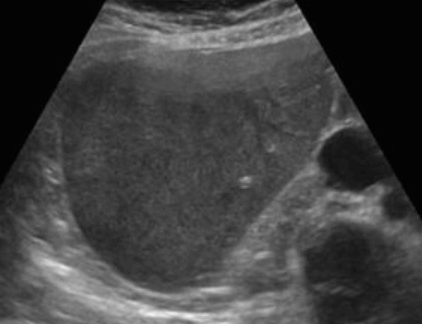

FNH의 경우 초음파소견은 다양하다. 병변은 등에코, 저에코, 고에코의 균질한 덩어리로 나타날 수 있다. 간내 혈관을 대체할 수 있는 대량 효과가 있다. 단지 18%의 사례에서만 중앙 흉터(저에코성 센터)가 존재한다. 이는 간혈관종과 매우 유사해 보인다. 또한 혈관 기형부위와 관련이 있다. 일반적으로 5cm 미만이다.

FNH (Focal Nodular hyperplasia) US finding

- spokewheel vascularity

- iso-hyperechoic mass

- hypoechoic lesion with central scar

- fatty liver

- isoechoic lesion

- central feeding artery

위에서 보인 초음파소견처럼 FNH는 경계가 명확한 균일한 종괴이며 내부에 섬유성 반흔이 있다. 에코는 저에코를 갖지만 간혹 고에코나 등에코등 다양하게 나타날 수 있으며 피막이 없다. 도플러상 과혈관성을 보이며 정상 간세포조직을 갖는다. 초음파 만으로 간암과 구별할 수 없으므로 혈액검사, CT 와같이 다양한 검사를 통한 진단이 필요하다.